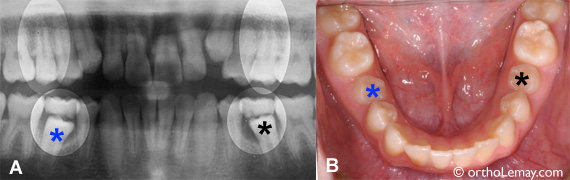

(A) À l’arcade inférieure, les dents temporaires préservent l’espace jusqu’à la sortie des deuxièmes prémolaires (*). À l’arcade supérieure, les prémolaires sont déjà sorties et l’espace de dérive est disparu. (B) Une fois les temporaires tombées, les prémolaires peuvent sortir convenablement dans l’espace disponible qui a été préservé. (Les * correspondent aux même dents en (A) et (B) )